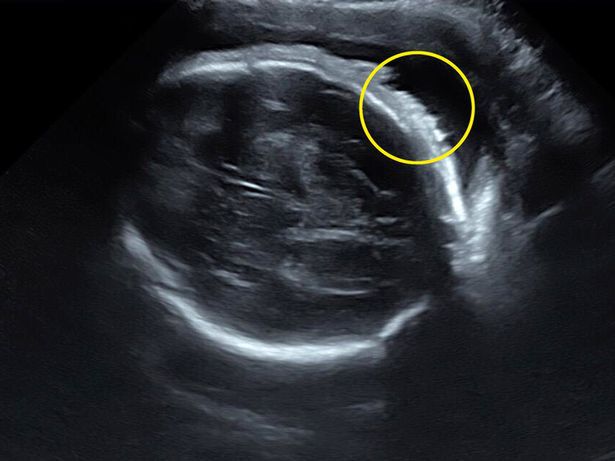

Lekarz wykonywujący badanie USG zatrzymał się na chwilę, ukazując główkę dziecka z profilu. Na jej wierzchołku było widać cienkie białe linie. Lauren początkowo nie wiedziała, na co patrzy, lecz z czasem zrozumiała, że były to włoski jej dziecka.

"Nawet nie wiedziałam, że można zobaczyć włosy na USG – wspomina. – Mówi się, że jak dziecko ma bujną czuprynę, to w czasie ciąży mama walczy ze zgagą. Jednak w moim przypadku nic takiego nie miało miejsca".